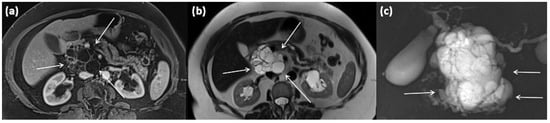

Figure 1.

Axial (a) and coronal (b) contrast-enhanced computed tomography of the abdomen in venous phase in a 74-year-old male patient. In the processus uncinatus, a sharply demarcated pseudocyst (arrows) without solid components, septa, or surrounding infiltration can be seen. At most, the pseudocystic wall shows mild contrast enhancement.

Figure 11.

Axial CT in portal venous phase (a) and axial MRI with T1w after gadolinium-based contrast administration (b) as well as T2w native (c) in a 64-year-old female patient. In the pancreatic body, a sharply demarcated, roundly configured, cystic lesion is present, fit to a branch duct IPMN (arrows). There are no main duct dilatation, solid parts, or vegetations. T2w shows a homogenous hyperintense signal.